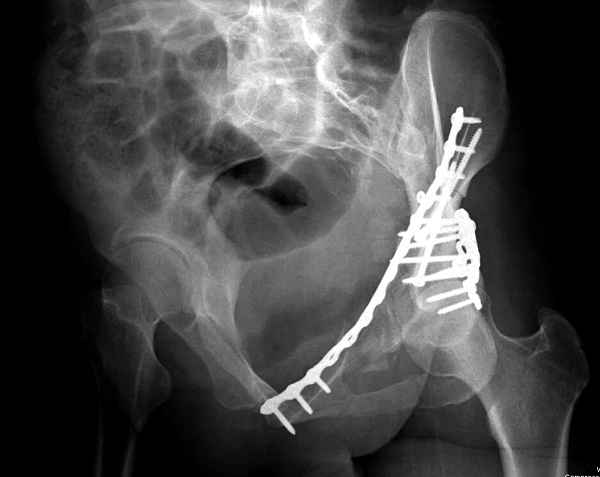

По-моему, надо готовить больного к будущей артропластике, но без опоры на задний столб невозможно удержать протез. Опорная конструкция (кольца и т.д.) должны иметь опору, и поэтому мы бы сделали реостеосинтез задним доступом. При надобности остеотомия и рутинная фиксация с межколонными винтами.

В дальнейшем, время покажет, когда приступить к артропластике....

Здесь несколько вариантов двухколонных свежих переломов, которые были оперированы из одного-заднего, а также из двух: переднего и заднего доступов.